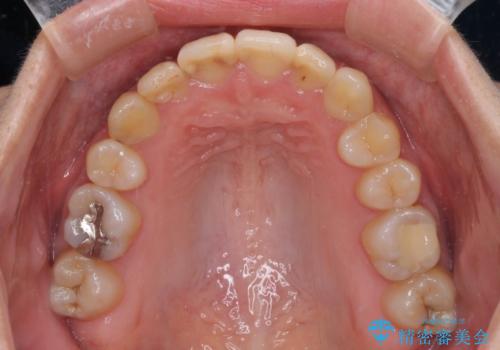

- 上下の八重歯を気にして来院された患者様です。

八重歯の後ろの歯を1歯抜歯し、補助装置(リンガルアーチ)を用いて八重歯の位置を改善し、その後インビザラインにより矯正治療を行うこととしました。

右側のみ上下小臼歯を抜歯したため、上下の正中が右にずれてしまう可能性があります。

また、元々右側は上下が咬み合っていないため、矯正をしても咬み合わないことも考えられました。

治療期間はかかりましたが、正中も合い、綺麗な仕上がりとなりました。